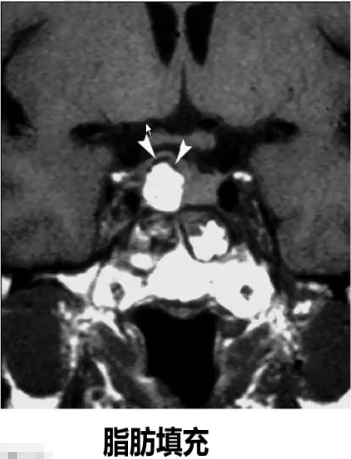

3、手术后高信号:手术填充材料(明胶海绵、脂肪);海绵窦受压血流减慢;手术区组织致密;残存垂体前叶激素分泌旺盛